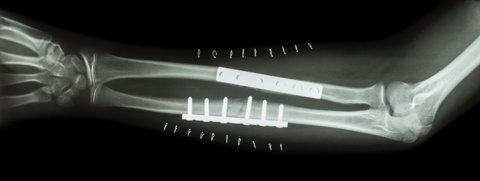

Severity and location are the key factors in treating a broken bone. An X-ray will highlight the extent of the damage and a competent medical professional will advise on the appropriate action.

Treatments for fractures can range from basic remedies such as splints, painkillers and plaster casts, through to more complicated procedures such as bone fracture surgery.